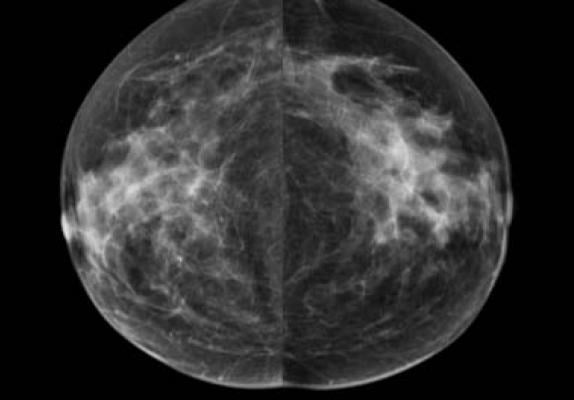

The densitasdensity software provides an automated mechanism for quantifying and recording percent breast tissue density, and making it readily available to the radiologist. Beyond speeding and simplifying the process of quantifying breast density, densitasdensity standardizes the density measurement. This enables uniform application of risk-based stratification of screen-eligible women aimed at ensuring those who need more aggressive follow-up receive it, while those who do not need aggressive follow-up do not receive unnecessary imaging. Densitas said the software is unique because it assesses breast density using the routinely archived processed DICOM images that radiologists normally review, and therefore supports prospective and retrospective breast density measurement for clinical care and for research.

densitasdensity was demonstrated at the Radiological Society of North America (RSNA) 2018 annual meeting, Nov. 25-30 in Chicago.